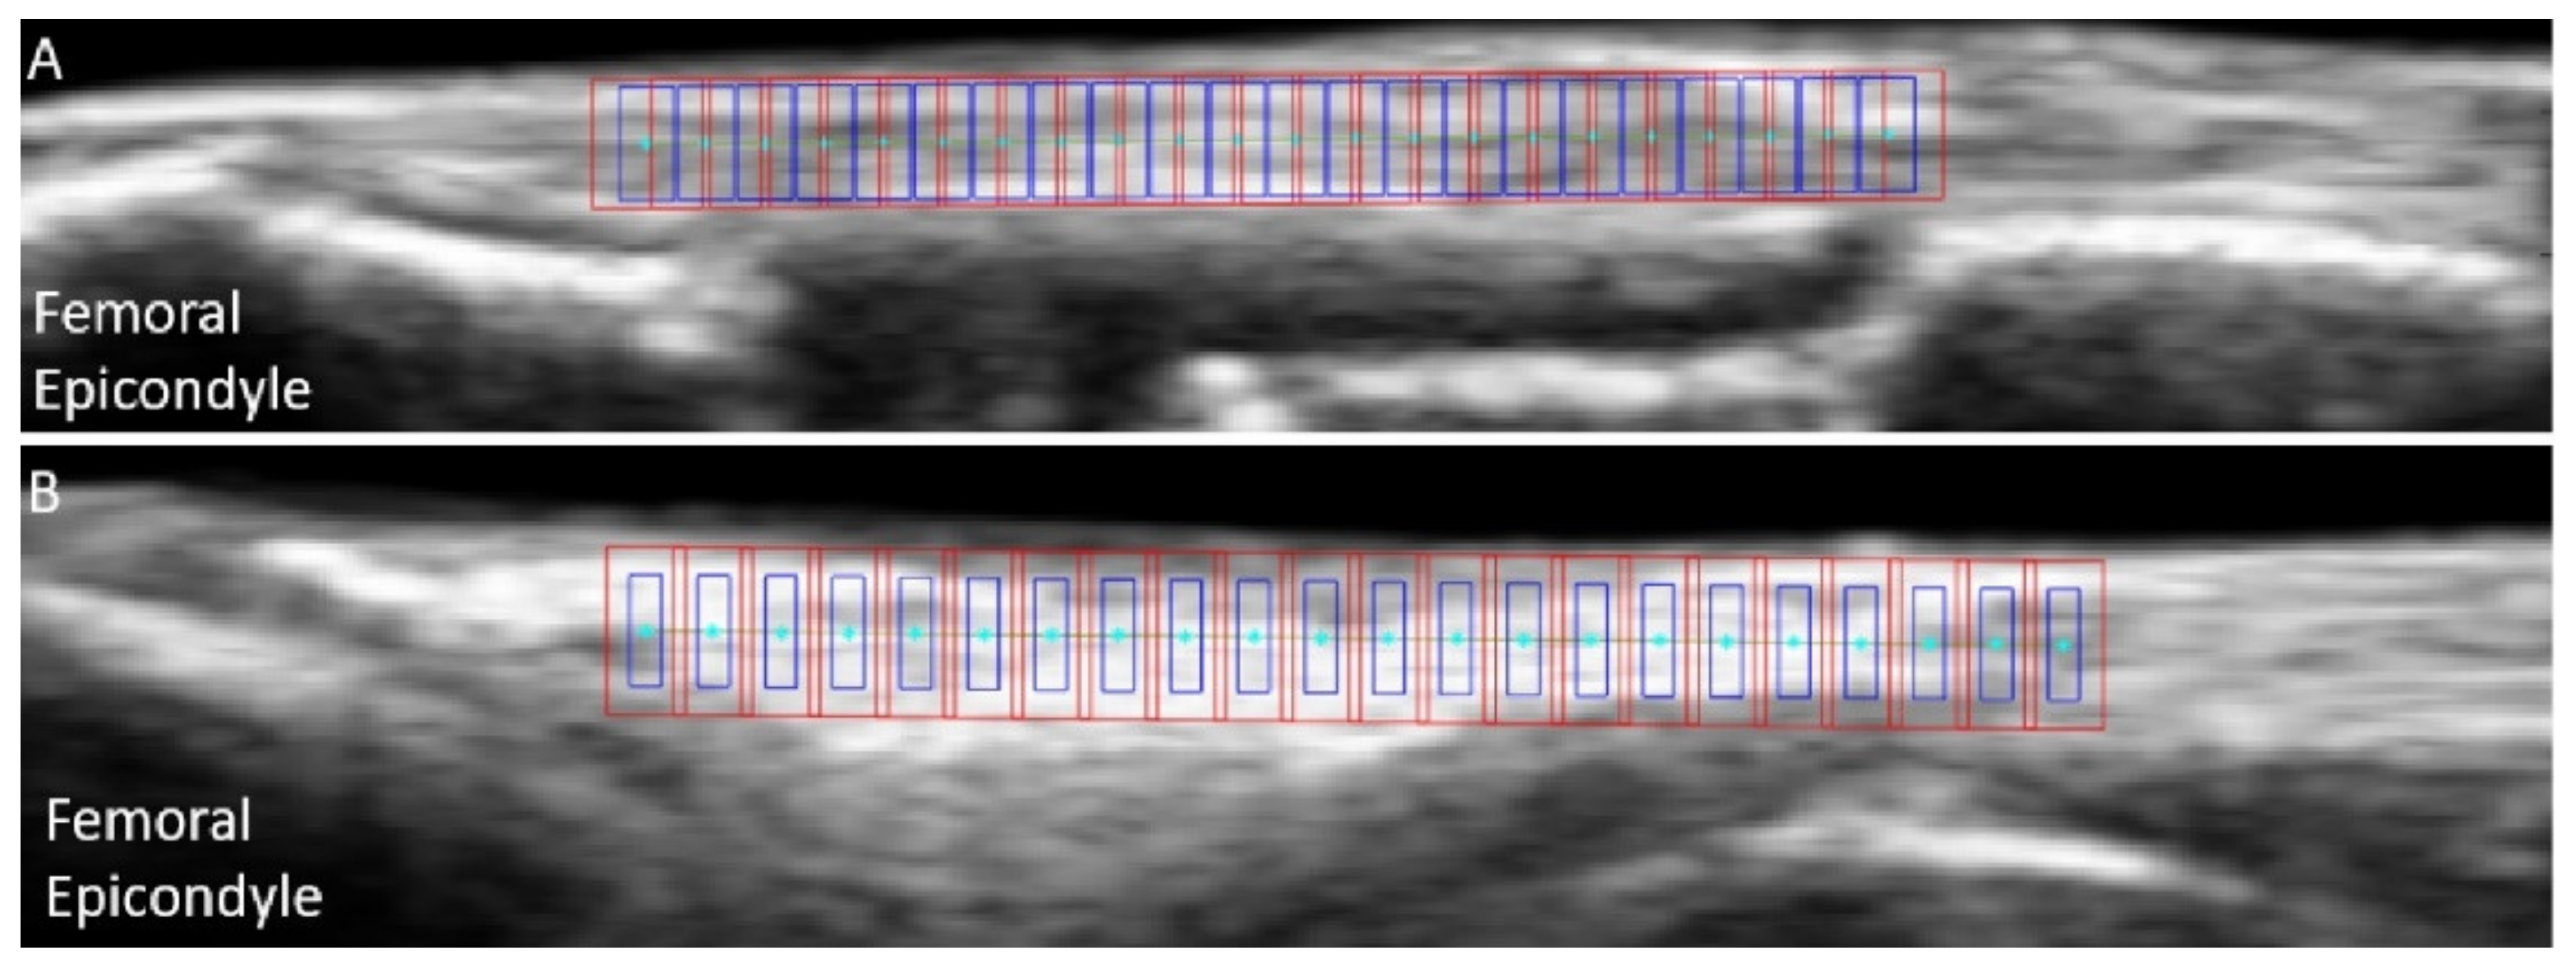

In the first pre-tracking phase, the quality of the cropped US images was subjectively assessed a second time, and trials presenting a clear transducer motion, implant artefact or important out-of-plane motion were excluded (25% of the discarded trials for both LCLs and MCLs). For good quality trials, the nodes were defined on the ligament’s b-mode image around the joint line, using the lateral (LCL) or medial (MCL) femoral condyles as anatomical references. The superficial and deep borders of the ligament were manually outlined. Then, equidistant nodes were automatically placed along a line of 18 mm of length positioned at 50% of the ligament depth, with a 0.8-mm inter-node distance (Figure 3). Two additional points were added to allow tracking the superficial border of the ligament. Afterwards, RF data were upsampled by a factor two and four along the image x- and y-axis respectively, to increase the spatial density for further correlation analysis [19].

Figure 3.

Example of initial nodes positions (cyan) overlaid on b-mode ultrasound images of the medial collateral ligament (A) and lateral collateral ligament (B), with the associated kernels (blue) and search windows (red).